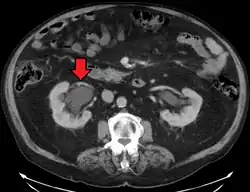

Stone causing hydronephrosis[16]

-